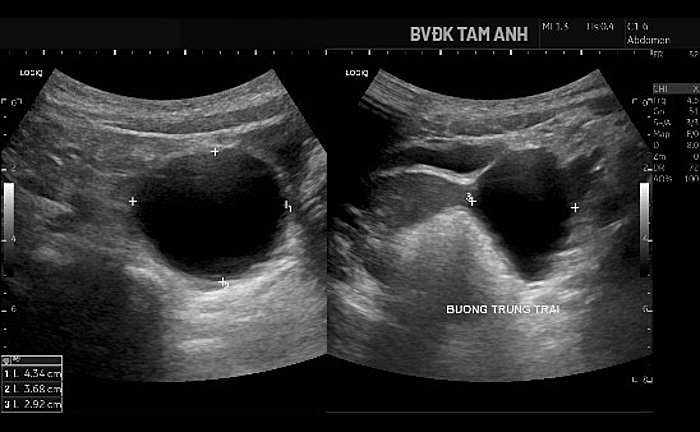

Beyond breast development, Huyen showed no other signs of puberty. Doctor Do Tien Son, head of Pediatrics at Tam Anh General Hospital Hanoi, noted the child's mammary glands had developed to Tanner stage B3, a phase characterized by rapid and clear appearance of breast tissue. The left ovary contained a large cyst, approximately 43x37x29 mm, with thin walls and clear fluid, containing a smaller cyst inside. The lesion was classified as ORADS 2, indicating a low risk of malignancy. MRI confirmed the left ovarian cyst was benign. X-ray results showed no increase in bone age, which currently matched the child's chronological age.

Ultrasound image showing the enlarged ovarian cyst. Photo: Tam Anh General Hospital |